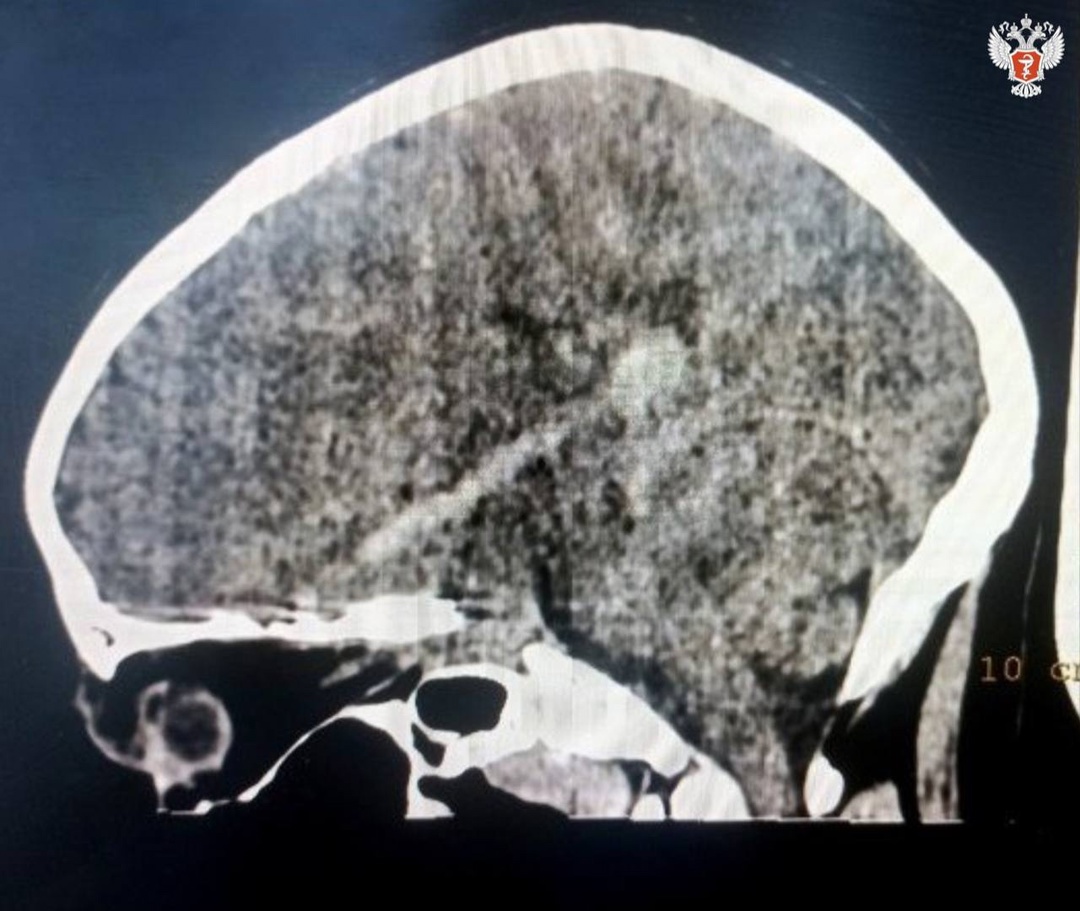

⚡️ Мальчику диагностировали открытую проникающую рану головы, ушиб головного мозга, внутримозговую гематому вдоль полости раневого канала, перелом основания черепа.

➡️ Однако из-за повреждения мозга у мальчика начался правосторонний гемипарез — ослабленность мышц с одной стороны туловища. Ребенок с трудом двигал правой рукой и ногой.